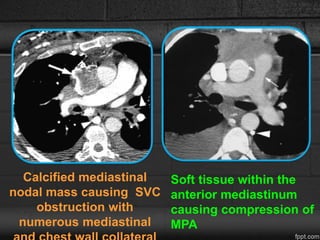

Imaging Manifestations

CXR

• widened mediastinum with hilar prominence and calcified lymph

nodes.

• Lobar volume loss - airway stenoses.

CT

• Infiltration of the mediastinum with abnormal soft tissue

• extensive lymph node calcification- H. capsulatum.

• extensive collateral vein formation due to fibrotic involvement of

systemic thoracic veins such as the SVC or azygos vein.

• Pulmonary artery compression may be visualized directly.

Calcified mediastinal

nodal mass causing SVC

obstruction with

numerous mediastinal

Soft tissue within the

anterior mediastinum

causing compression of

MPA

• 62.

Calcified mediastinal nodal masscausing SVC obstruction with numerous mediastinal Soft tissue within the anterior mediastinum causing compression of MPA